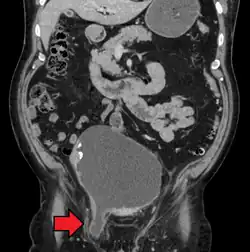

Medical imaging

A physician may diagnose an inguinal hernia, as well as the type, from medical history and physical examination.[20] For confirmation or in uncertain cases, medical ultrasonography is the first choice of imaging, because it can both detect the hernia and evaluate its changes with for example pressure, standing and Valsalva maneuver.[21]

When assessed by ultrasound or cross sectional imaging with CT or MRI, the major differential in diagnosing indirect inguinal hernias is differentiation from spermatic cord lipomas, as both can contain only fat and extend along the inguinal canal into the scrotum.[22]

On axial CT, lipomas originate inferior or lateral to the cord, and are located inside the cremaster muscle, while inguinal hernias lie anteromedial to the cord and are not intramuscular. Large lipomas may appear nearly indistinguishable as the fat engulfs anatomic boundaries, but they do not change position with coughing or straining.[22]